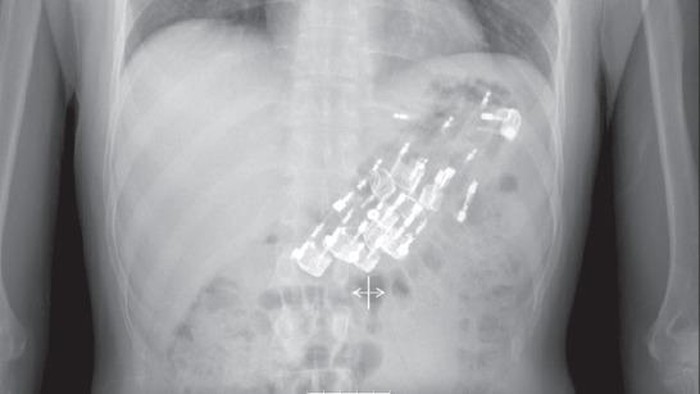

Dokter di Turki menemukan 10 korek api berukuran 8x2 cm di dalam perut seorang pasien pria berusia 28 tahun. Pasien itu dibawa ke rumah sakit setelah mengalami nyeri perut, mual, dan muntah selama 2 hari. (Foto: Jurnal Northern Clinics of Istanbul)

Pasien rupanya sudah didiagnosis penyakit mental skizofrenia, tapi tidak sedang menggunakan obat anti-psikotiknya, sehingga diduga menelan korek api tersebut. Ketika dilakukan operasi, diketahui sembilan korek api berada di lambung dan satu sudah masuk usus. (Foto: Jurnal Northern Clinics of Istanbul)